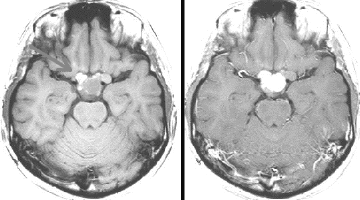

9歳男児の松果体奇形腫です。生検術と第3脳室開窓術を受けましたが,摘出術のリスクが高すぎるということで化学療法を6コース。2年間経過観察されましたが,腫瘍が増大しました。私のところへ来た時には,前後径73mmありました。

左からT2, swan, T1です。これが 類皮のう胞 dermoid cyst ということがわかります。類皮のう胞単独,あるいは成熟奇形腫の大部分としての類表皮のう胞は,かなり頻度の高いものです。松果体腫瘍で奇形腫を疑ったらまず,類皮のう胞の混在を疑います。それがあれば,かなりの確率で成熟奇形腫 mature teratomaです。

類皮のう胞は内部がほとんど皮脂,ケラチン,汗,毛髪なので,簡単に砕けるし,掻き出し吸い取ることができます。松果体成熟奇形腫の中では最も戦いやすい相手と言えるでしょう。再発しないようにするには,周囲ののう胞壁(真の腫瘍細胞)を完全摘出するしかありません。放射線も化学療法も何も効かないし,のこせば必ず再発します。

右迂回槽にちょっとdebrisは残っていますが完全摘出できました。病理は他の成分を少し混じる成熟奇形腫です。術後3年間再発はありませんし,学校へ通って体育もできています。

この手術はもちろん簡単ではありません,でもほとんどが類皮のう胞であるということがわかったので踏み込めたのです。